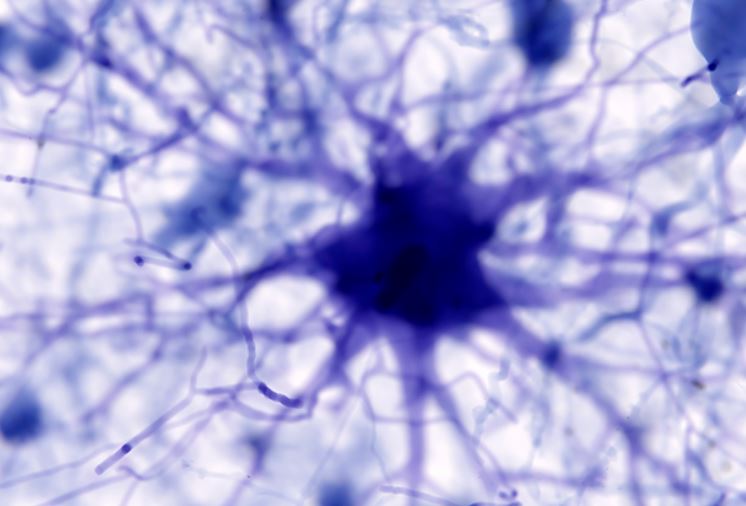

Các tế bào não được gọi là tế bào hình sao có thể là một trong những chìa khóa dẫn đến bệnh Alzheimer. Ảnh: Getty